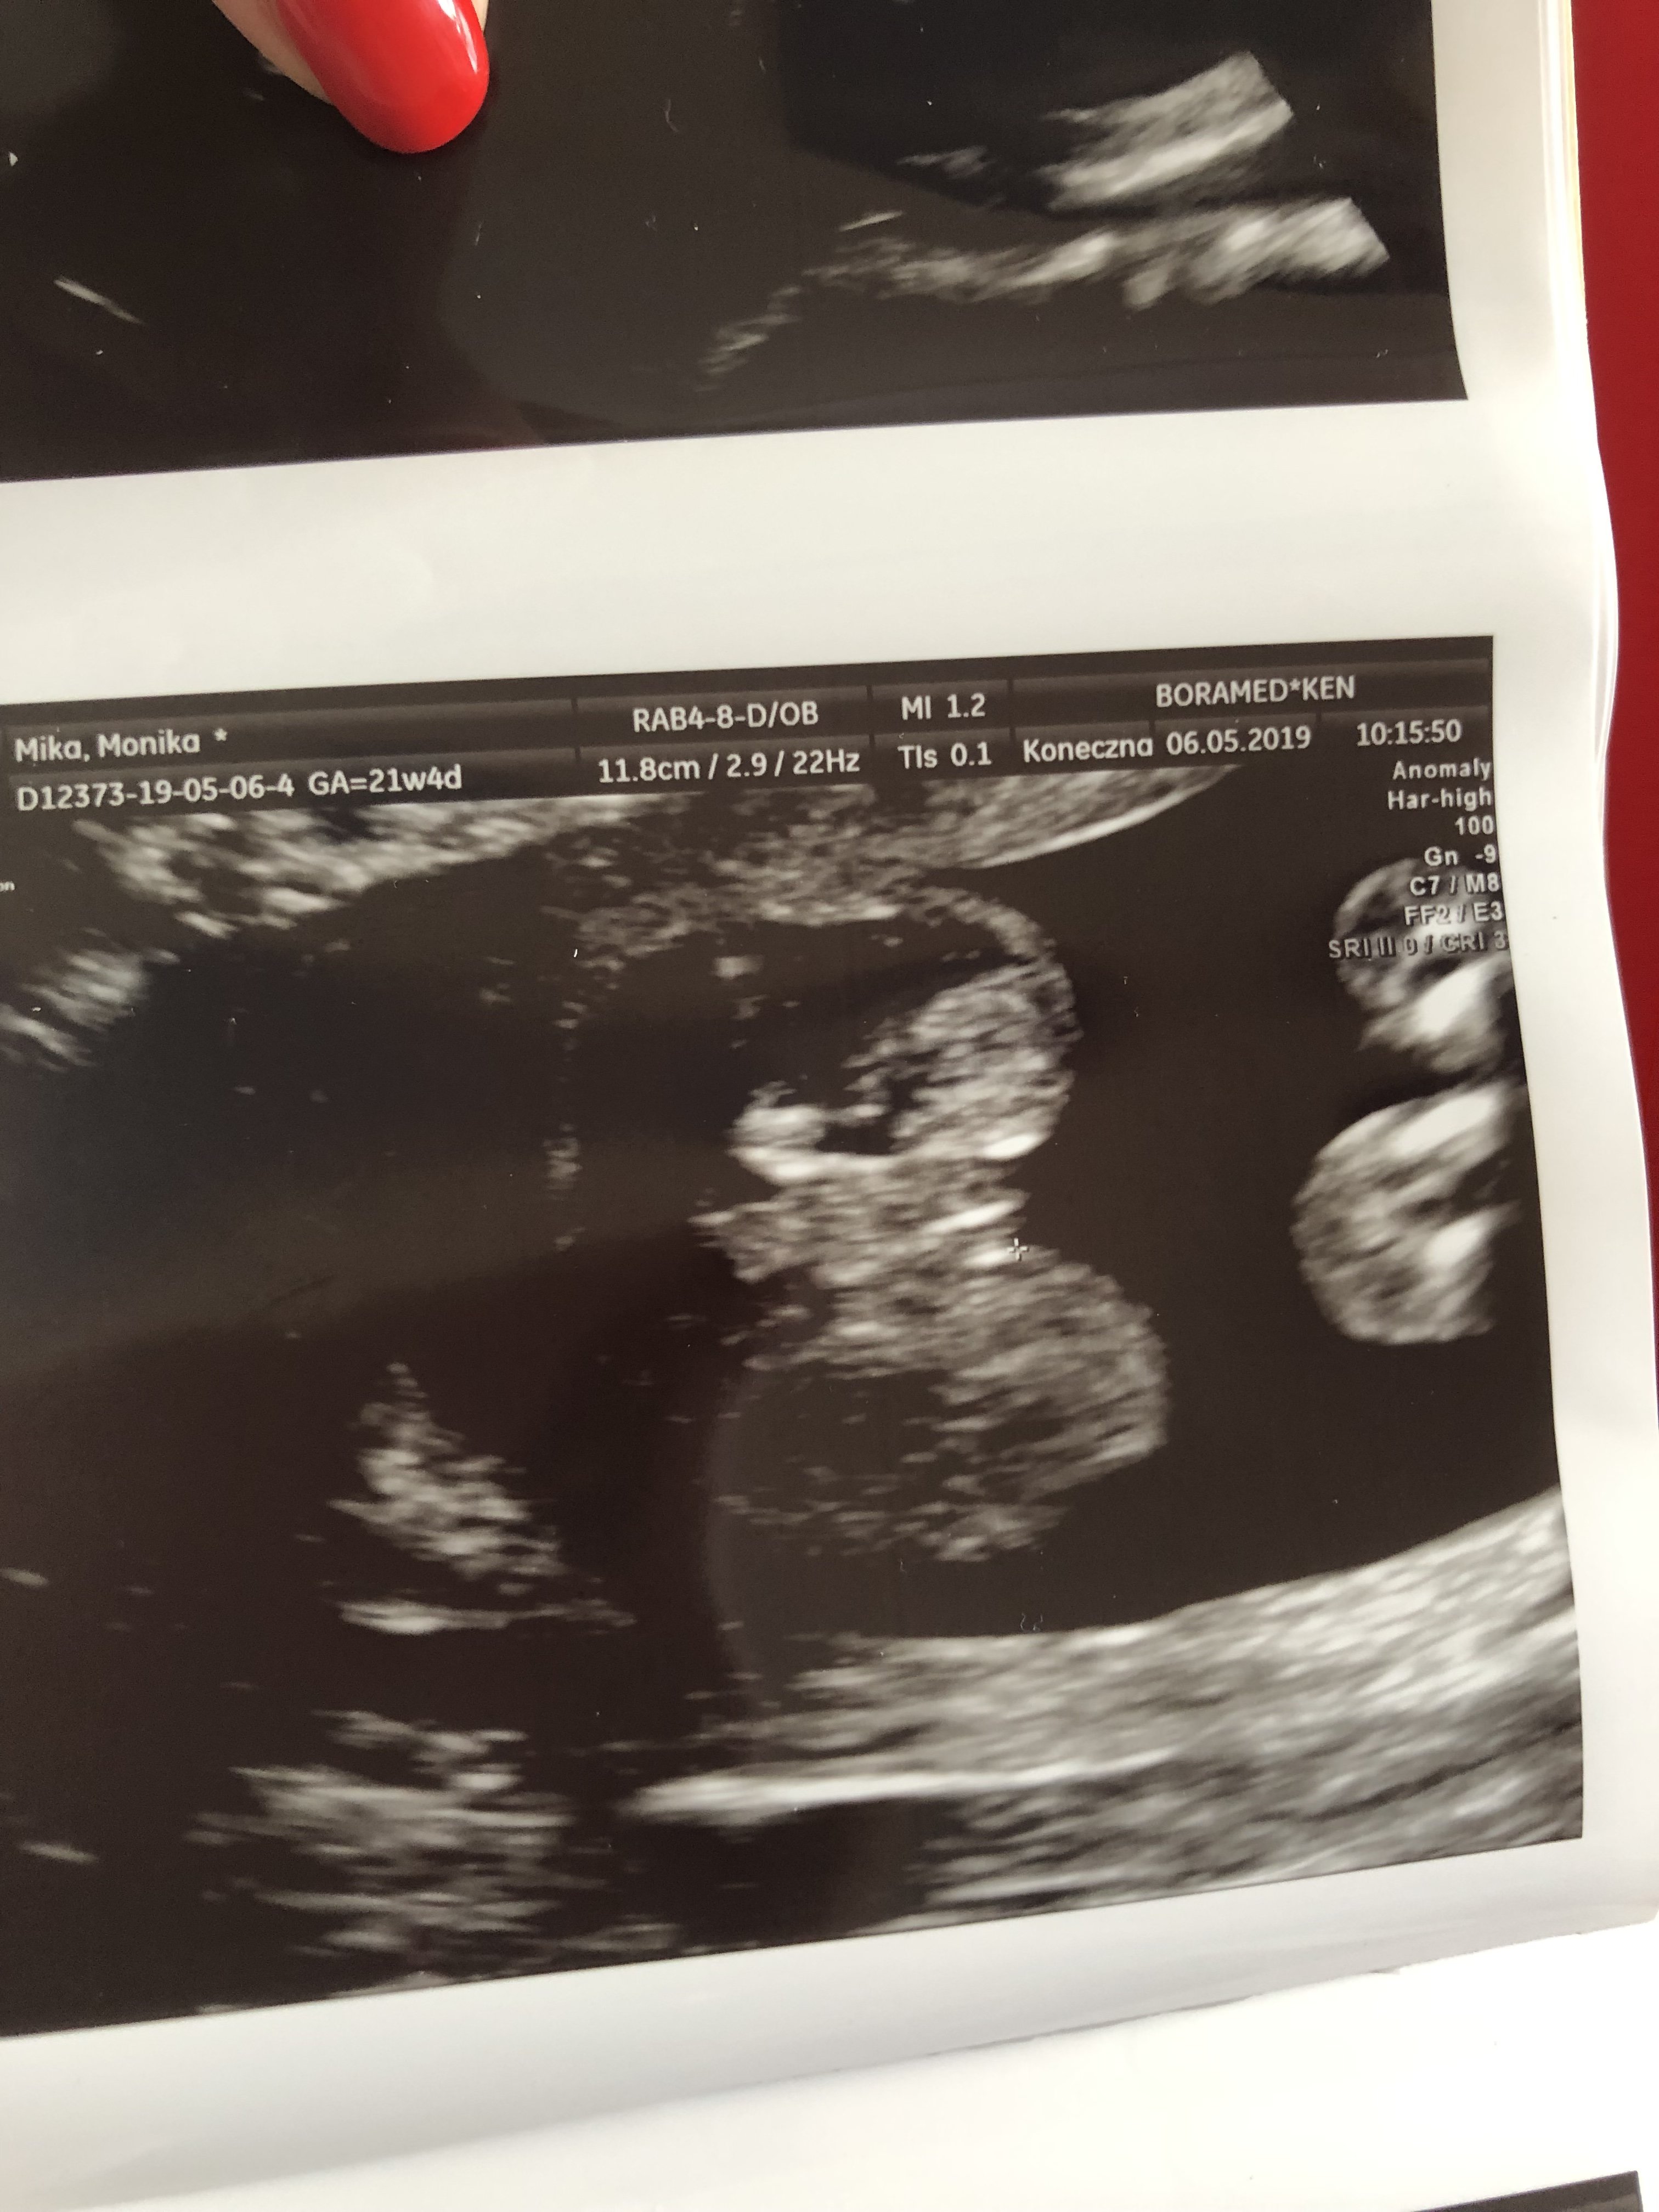

Witajcie dziewczyny.

Byłam na badaniu i lekarz powiedział, że chłopiec, ale nie da sobie za to ręki uciąć hehe . Teraz nie mogę spać, myśleć i normalnie funkcjonować hehe czy wy też myślicie, że to mój wymarzony synuś?

Załączniki

• IMG_20190503_160544.jpg

IMG_20190503_160544.jpg

1,4 MB · Wyświetleń: 460

• IMG_20190503_160248.jpg

IMG_20190503_160248.jpg

1,2 MB · Wyświetleń: 428